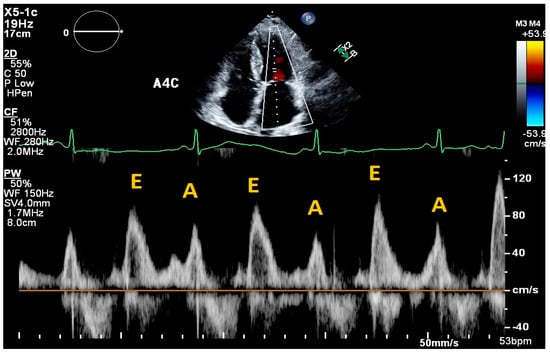

2. Cardiac Ultrasound

| Transthoracic Echocardiography | ||||||

| Simioniuc et al., 2016 [8] | Retrospective cohort | Doppler echocardiography: mitral inflow velocities | Outpatient HF patients | Outcomes and renal function in outpatients with HFrEF who received echocardiography/BNP-guided therapy vs. standard of care | n = 1137 | Decreased mortality in the echo–BNP group (HR 0.45, 95%CI: 0.30–0.67, p < 0.0001) and decreased rates of renal dysfunction (HR 0.49, 95%CI 0.36–0.67, p < 0.0001). |

| Modality | Measure | Normal Range | Interpretation | Limitations |

| Cardiac Ultrasound | ||||

| Mitral E/e’ ratio estimated from the E wave velocity of the mitral inflow Doppler envelope and the tissue Doppler e’ wave velocity at the mitral annulus (septal and/or lateral) | E/e’ ≤ 14 |

|

| |

| DT in the mitral inflow Doppler envelope | 160–200 ms |